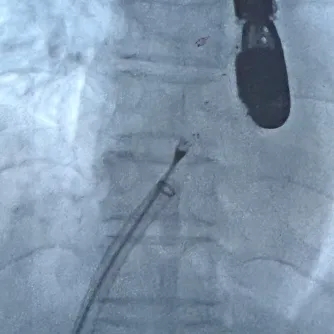

术中复测:术中食道超声下复测缺损大小,缺损大小为14.5mm,合并软缘11.7mm,其他边缘充足。

封堵策略:考虑到缺损的软缘范围较大,且房间隔总长足够,选择BDASD-Ⅰ30可降解房间隔缺损封堵器,配合I-16F可降解封堵器介入输送系统实施封堵。

术中复测

术中测量软缘长度

术中复测缺损大小

剑下双房心切面测量上腔静脉侧边缘